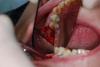

SergeyAL Опубликовано 28 мая, 2013 Поделиться Опубликовано 28 мая, 2013 на кт представлена ситуация до пластики в области 26, 27 зубов по косой линии проведен забор костного блока, блок разделен на пластины, с пластин получена костная стружка проведен вертикальный разрез с преддверия с переходом на окклюзионную поверхность гребня и на 0,5 см на небную поверхность проведена ШИРОКАЯ ОТСЛОЙКА: вестибулярно до бугра, окклюзионно до бугра, небно почти до небного шва и до бугра, слизистая должна сниматься с гребна как чулок (на отек не влияет, т.к. нет послабляющих разрезов надкостницы) из пластин сформирован каркас, внесена костная стружка, через этот же доступ проведен открытый синуслифт, введен синтетическим остеозамещающий материал рана ушита простыми узловыми швами за счет перемещения тканей в небную сторону со сторны преддверия через 4 месяца кт для сравнения, и имплантация через 4 месяца протезирование сначала временное, затем постоянное 17 Ссылка на комментарий